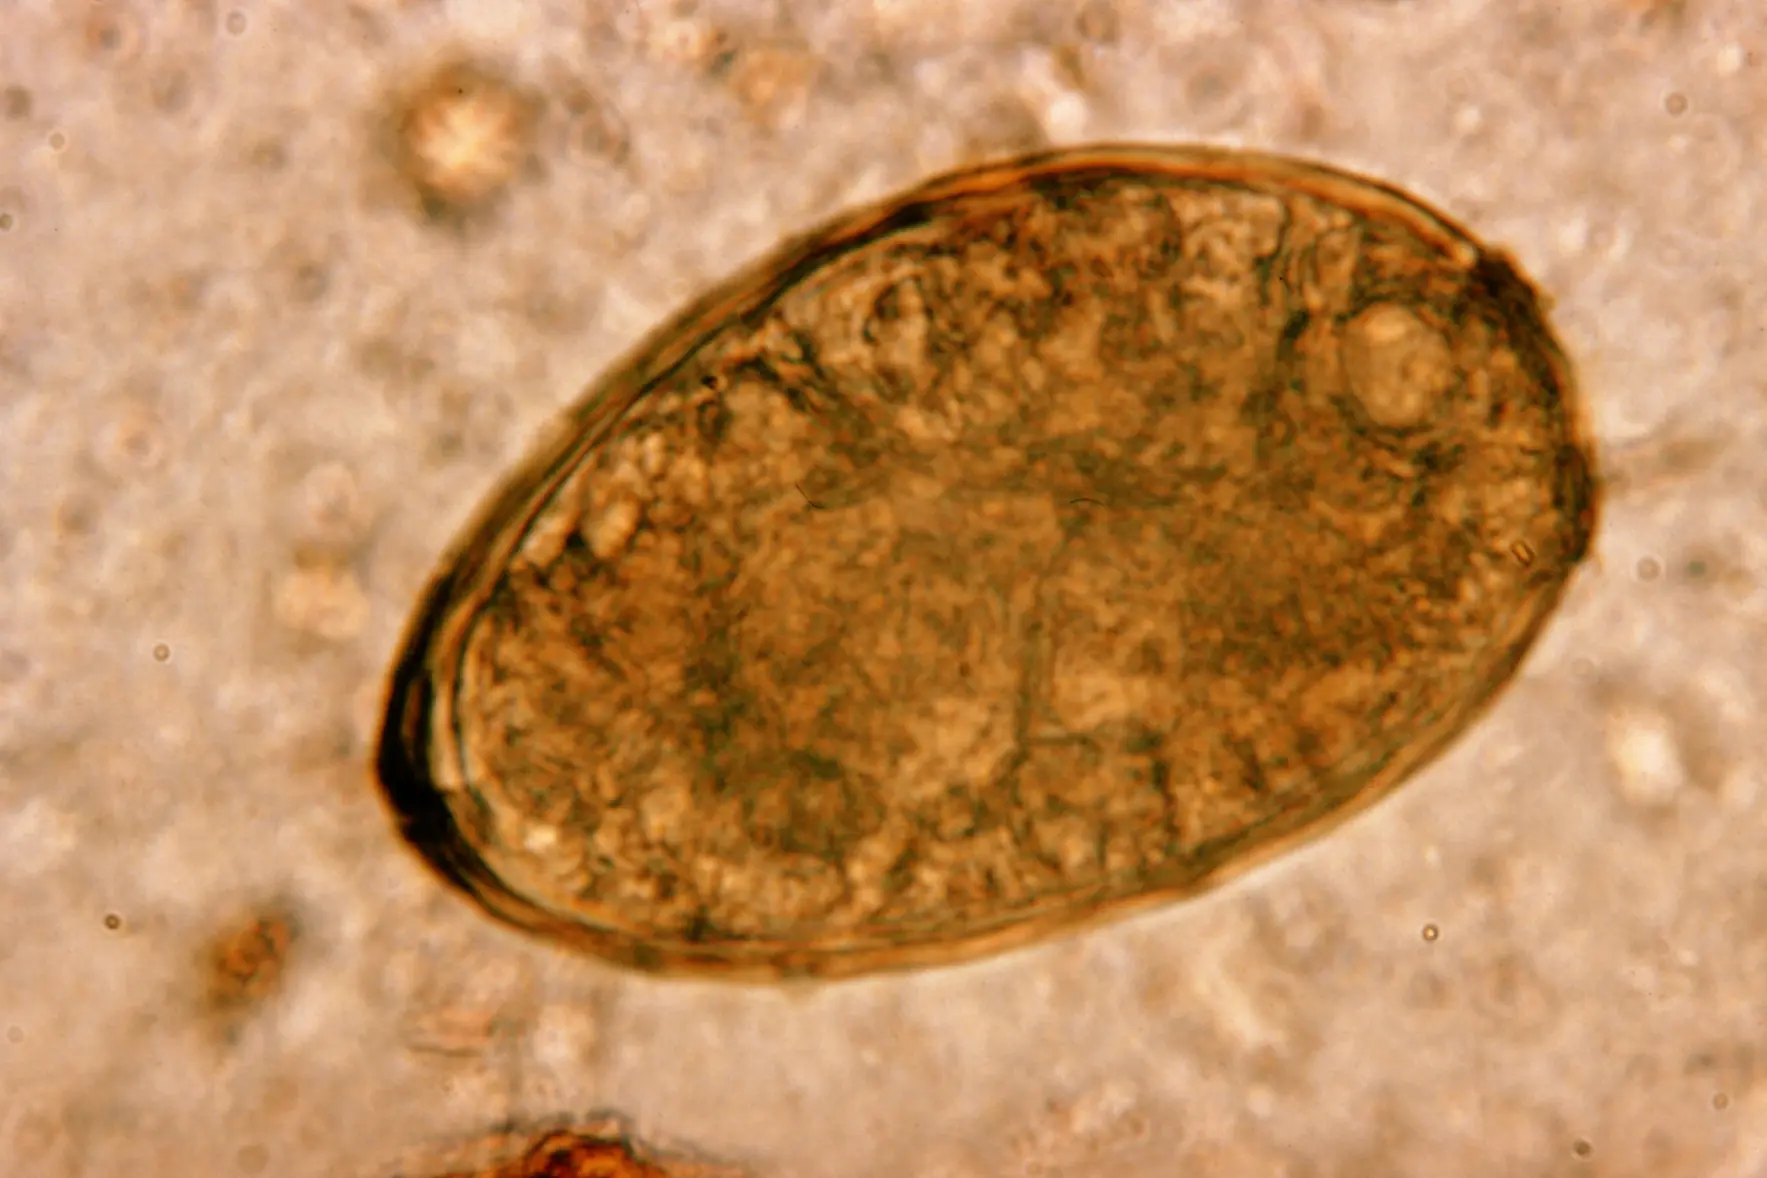

A lo largo de los módulos, aprenderás a identificar morfológicamente protozoos, helmintos y artrópodos, reconocer sus ciclos biológicos y comprender la relación parásito-huésped. Se abordarán en detalle los métodos de diagnóstico coproparasitológico, hemoparasitológico y tisular, junto con el uso de pruebas moleculares e inmunológicas modernas.

El programa integra conocimientos clínicos, epidemiológicos y de laboratorio, lo que te permitirá correlacionar hallazgos microscópicos con el cuadro clínico del paciente y con la realidad epidemiológica de tu región. Además, se incluirán casos clínicos reales, imágenes microscópicas de referencia y ejercicios prácticos, asegurando un aprendizaje aplicado y de alto nivel académico. Para más cursos relacionados, visita https://virtuallabint.com/cursos-laboratorio-clinico-online/

Imágenes microscópicas de referencia y fotografías de casos reales.